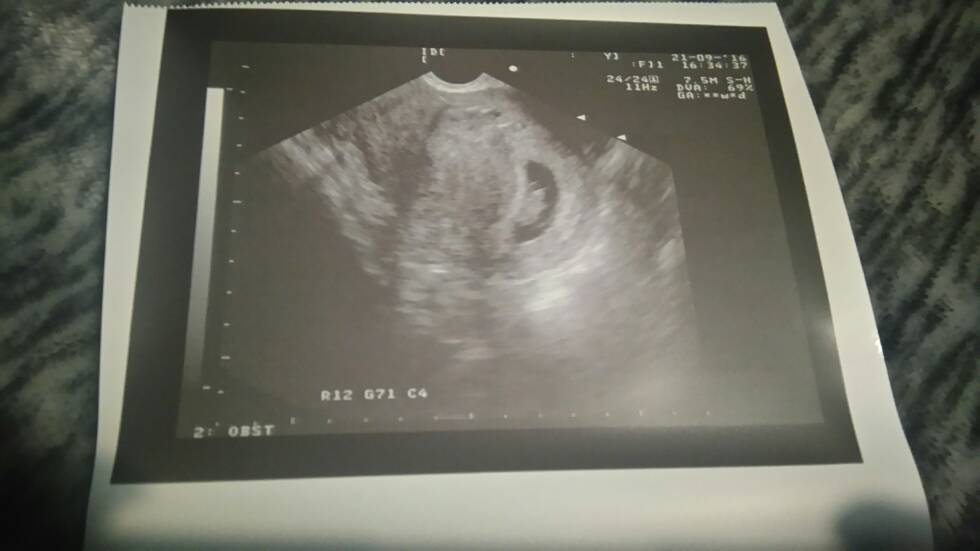

Melduję się po wizycie :-) pięknie bijące serduszko 170 razy na min, maluszek 13 mm, 7t5d. Termin z ostatniej @ 2.05 z usg 11.05. Mówił że ciąża może być młodsza. Za 4 tyg następna wizyta więc będzie, 12 tyg i wszystko bardziej szczegółowe